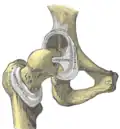

Та́зобе́дренный суста́в (лат. articulatio coxae) — чашеобразный, многоосный сустав, образованный полулунной поверхностью вертлужной впадины тазовой кости и суставной поверхностью головки бедренной кости. Вертлужная губа, сращённая с краем вертлужной впадины, углубляет последнюю.

Суставная капсула к тазовой кости прикрепляется по окружности вертлужной впадины, оставляя вертлужную губу внутри полости сустава. К бедренной кости капсула прикрепляется спереди вдоль межвертельной линии, сзади — немного отступая кнутри от межвертельного гребня. Таким образом, шейка бедра располагается в суставной полости.

Связка головки бедра (лат. ligaméntum cápitis fémoris), находящаяся внутри суставной капсулы, препятствует чрезмерному приведению и наружной ротации бедра. Кроме этой связки тазобедренный сустав укреплён несколькими толстыми, прочными связками, расположенными как в толще капсулы, так и на её поверхности, а именно:

Подвздошно-бедренная связка(lig.iliofemorale)

Лобково-бедренная связка(lig.pubofemorale)

Седалищно-бедренная связка(lig.ischiofemorale)

Связка головки бедренной кости(lig.capitis femoris)

Круговая зона